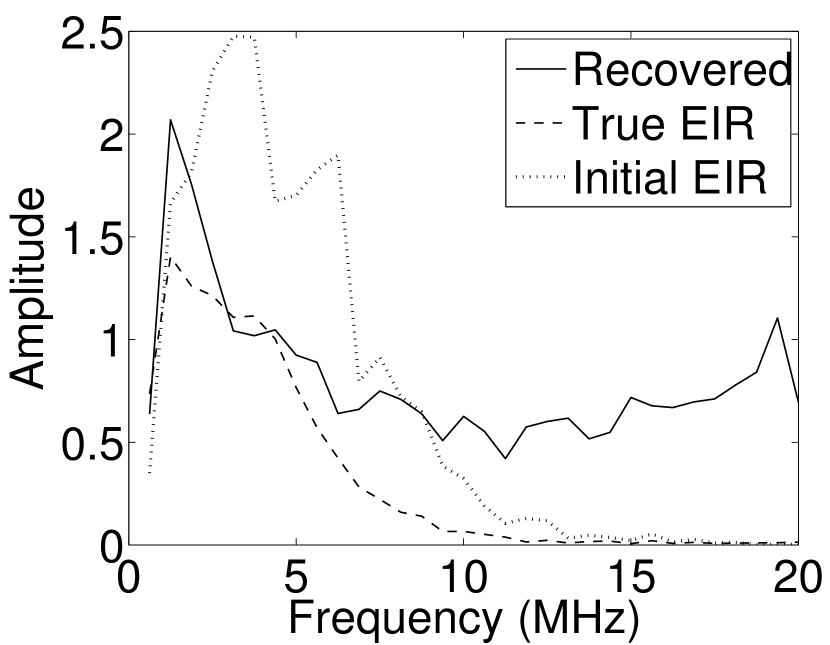

As shown in Figure 6, when the error in the EIR was small (e.g., as with the EIR in Figure 6(a)), images were reconstructed with high accuracy using the VP algorithm. When the perturbations in the EIR were stronger (e.g, as in Figure 6(c)), artifacts and distortions in the reconstructed images were still significantly reduced by use of the VP algorithm; however, larger values of the regularization parameters had to be applied. When as in the initial EIR in Figure 6(e), no improvement was observed in the image reconstructed by use of the VP algorithm.

Images reconstructed by use of the VP algorithm with different values of the regularization parameter values are shown in Figure 8. The recovered EIRs and their corresponding Fourier spectra are shown in Figures 9 and 10, respectively. The RMSE values are computed and displayed together with the corresponding images. As expected, the images reconstructed with smaller values of contain higher noise levels, while images using larger possess a reduced noise level. However, larger values of also caused artifacts in the reconstructed images. The same observation can be made for the effect of the regularization parameter on the recovered EIR. One also observes that the reconstructed images and EIRs depend continuously on the regularization parameters and , i.e. small changes in the regularization parameters cause minor changes in the reconstructed images and EIRs.